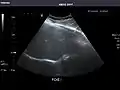

Renal ultrasonography

Ultrasonography of the kidneys is essential in the diagnosis and management of kidney-related diseases. The kidneys are easily examined, and most pathological changes in the kidneys are distinguishable with ultrasound.[7]

Right kidney

Kidneys: Right and left kidneys measure 11.5 cm and 12 cm in length respectively. No hydronephrosis. Small left lower pole kidney cyst.